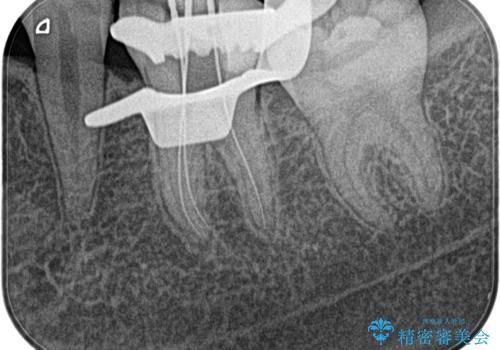

不可逆性歯髄炎の診断のもと根管治療を行なっております。

根管治療は1回ごとにまとまった時間で治療を行うことにより2~3回の治療で完了します。

治癒不良の場合は外科的歯内療法の適応となります。

根管治療した歯は、クラウン修復が必要です。